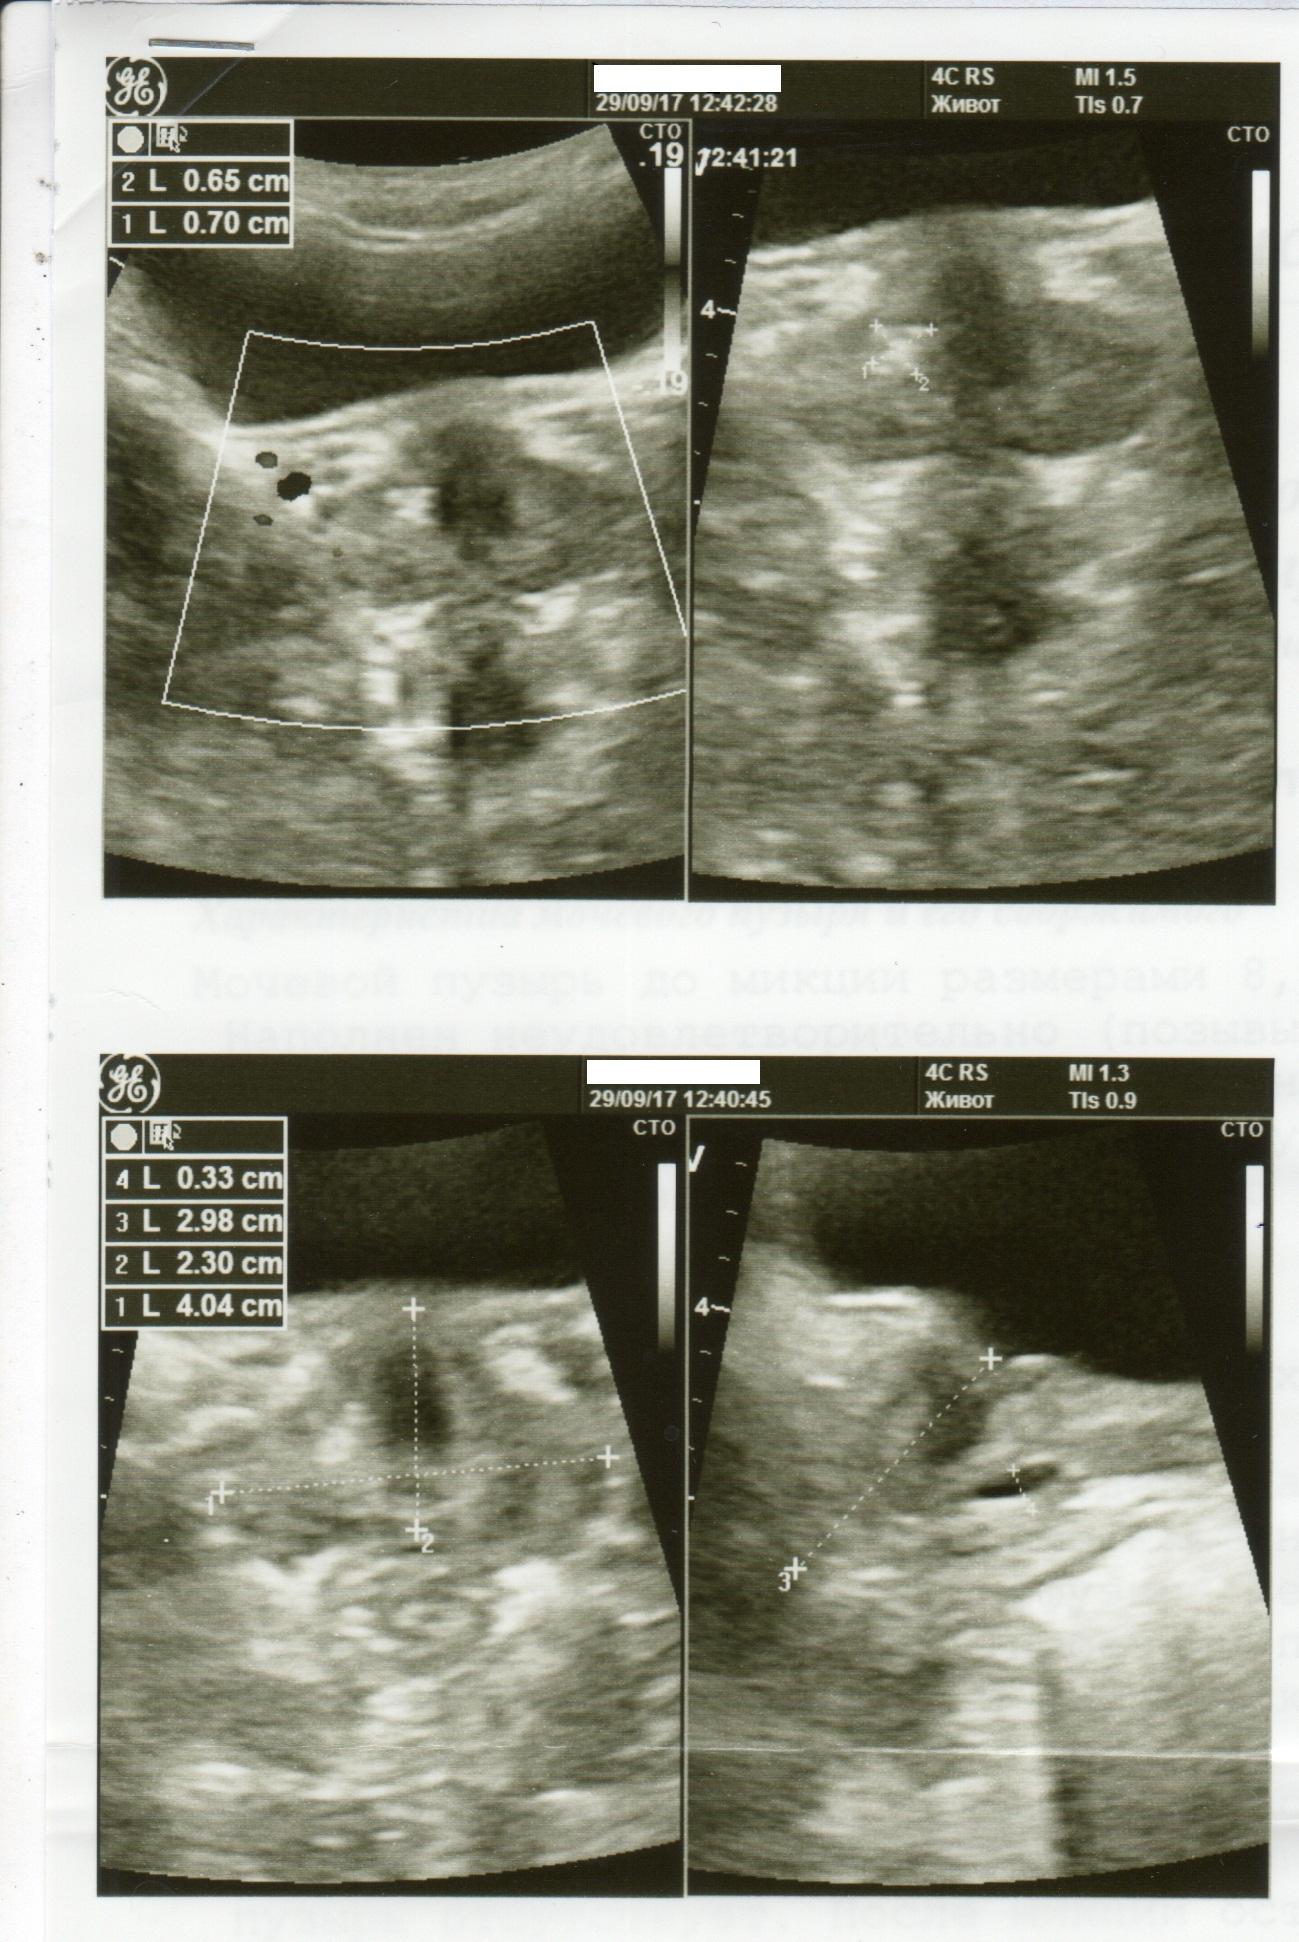

Здравствуйте. Мне 29 лет. Вес 60 кг. Рост 174см. Пол мужской. Беспокоят частые позывы к мочеиспусканию уже где-то пол года. От 6-8 раз в сутки. Раньше столько не ходил. Чувствую что мочевой пузырь не совсем полный. Где то 100-150мл и бегаю в туалет. Очень давно при прыжках с небольшой высоты была резкая боль в промежности. Сейчас очень редко бывает, не знаю простата это болит или что-то другое. Ночью встаю 1 раз. Струя нормальная. Делал УЗИ несколько раз. Врач пальцем проверил простату, сказал, что с левой стороны прощупываются неровности. Боли при ощупывании не было, было чувство на головке, как будто позыв к мочеиспусканию сильный. Сразу ершиком взял анализ ПЦР на инфекции. Нашли только гарднерелла. Сразу начал выписывать антибиотик. Я сказал, не лучше будет на чувствительность сделать анализ. Сказал, зачем терять время. У меня во вложении назначение, ответы анализа, УЗИ.

5. Из клиники только частые позывы. Есть какие то изменения в простате по УЗИ, но я до сих пор сомневаюсь есть ли у меня хр. простатит и какой именно(синдром тазовой боли, инфекционный и др.). Что еще нужно сделать, чтобы определиться с причиной частых позывов?